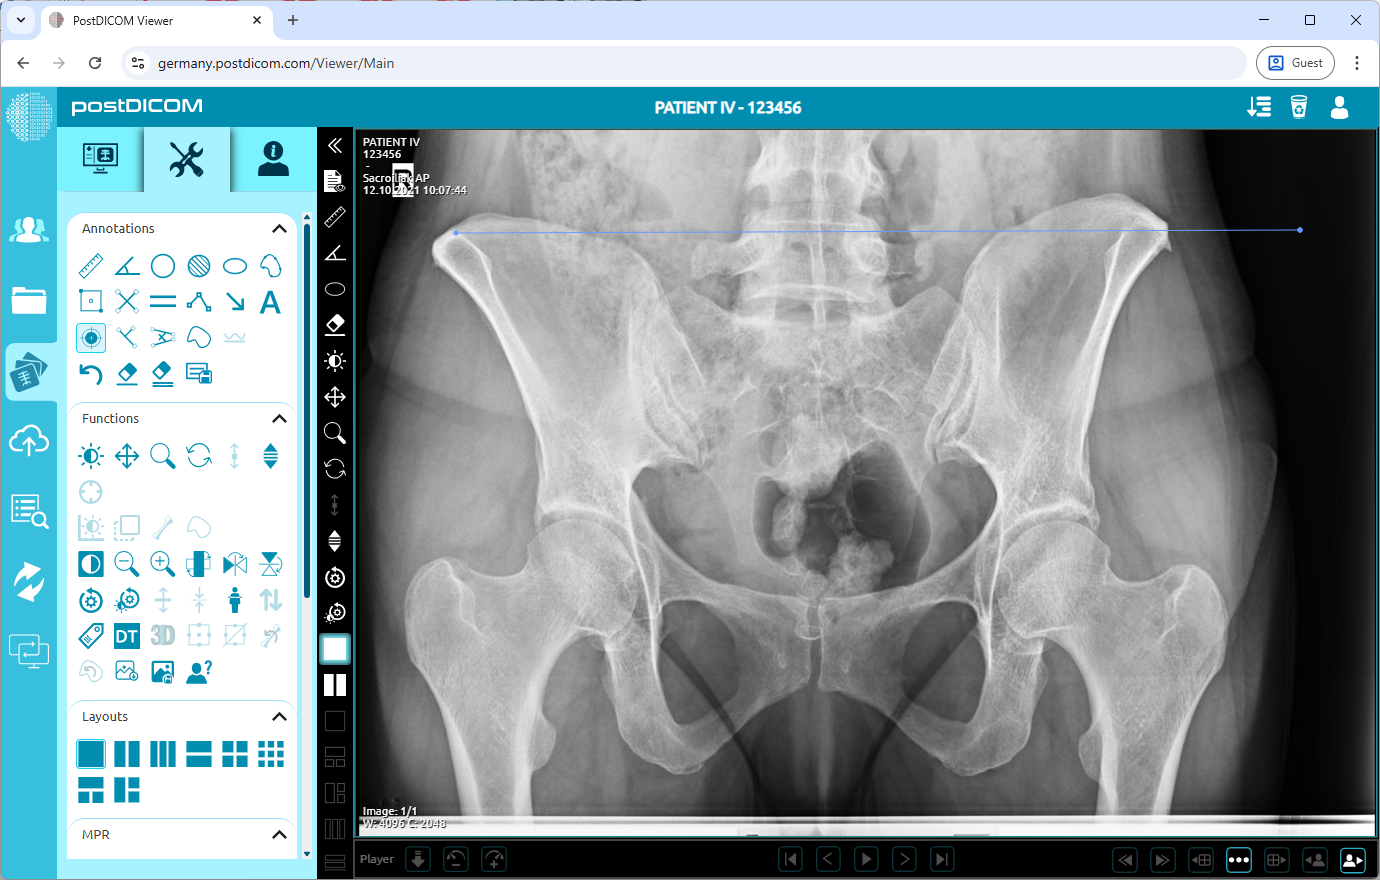

When you click on the icon, it will turn into blue color and a ruler sign will be shown at the bottom of your mouse pointer. Click on the starting point of the distance and move your mouse to the endpoint. Until you click, the distance will appear in blue. Click again to finish drawing the line.